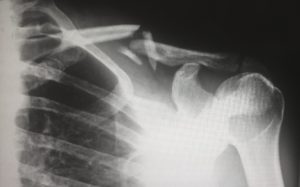

Dr. Paul Sethi M.D. states, “We are still giving out too many pills for any given procedure. So, rotator cuff surgery may get more than an average of ninety pills while joint replacements are going to get more than one-hundred pills.”